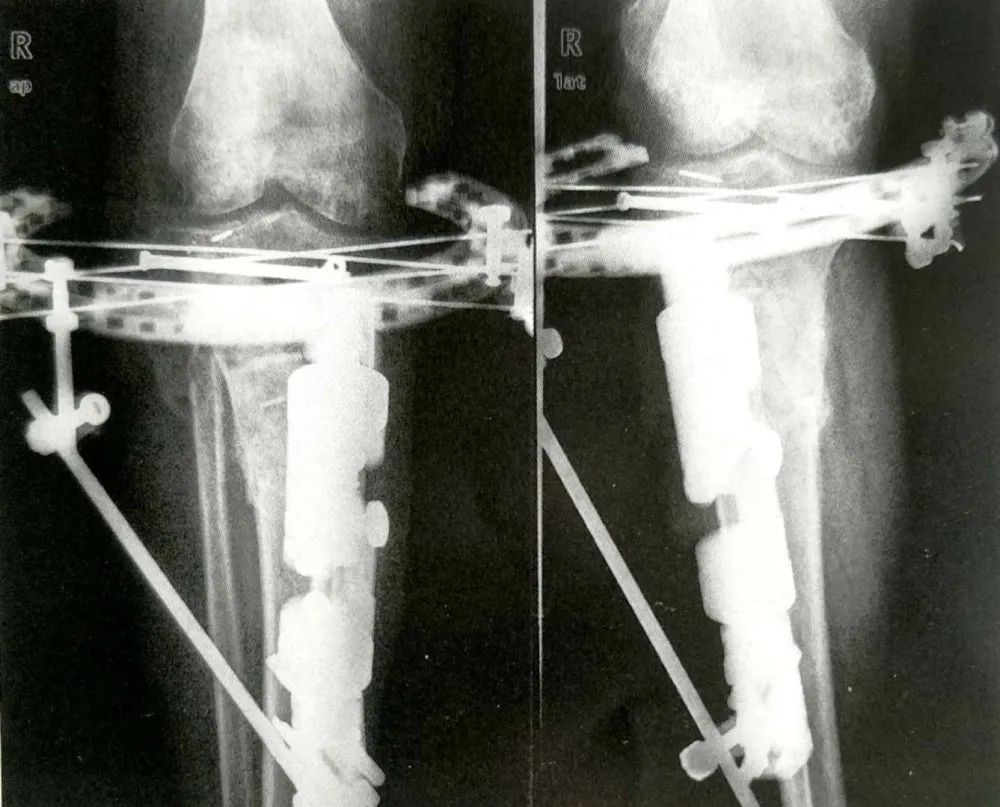

▲ 胫骨平台SchatzkerⅥ型骨折

A:术前正侧位X线片,可见胫骨平台关节面和干骺端粉碎性骨折;

C:有限切开复位,应用克氏针固定关节面骨块,同时行Hybrid外固定架固定,术后一周正侧位X线片显示关节面复位良好,胫骨轴线恢复正常;

D:术后8个月正侧位X线片可见骨折已基本愈合,与术后一周X片对比,没有复位丢失。